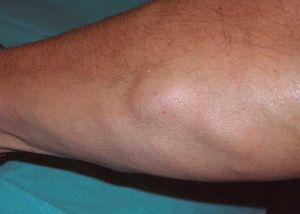

En la exploración física se observaban numerosos tumores subcutáneos en extremidades superiores, y en menor medida en tronco y extremidades inferiores, bien delimitados, de consistencia firme, algunos dolorosos al tacto (fig. 1). También presentaba un patrón lipodistrófico, con adiposidad central y lipoatrofia en cara y miembros.

Figura 1. Tumor subcutáneo en antebrazo, bien delimitado, de consistencia firme, no adherido a estructuras profundas, doloroso a la palpación.